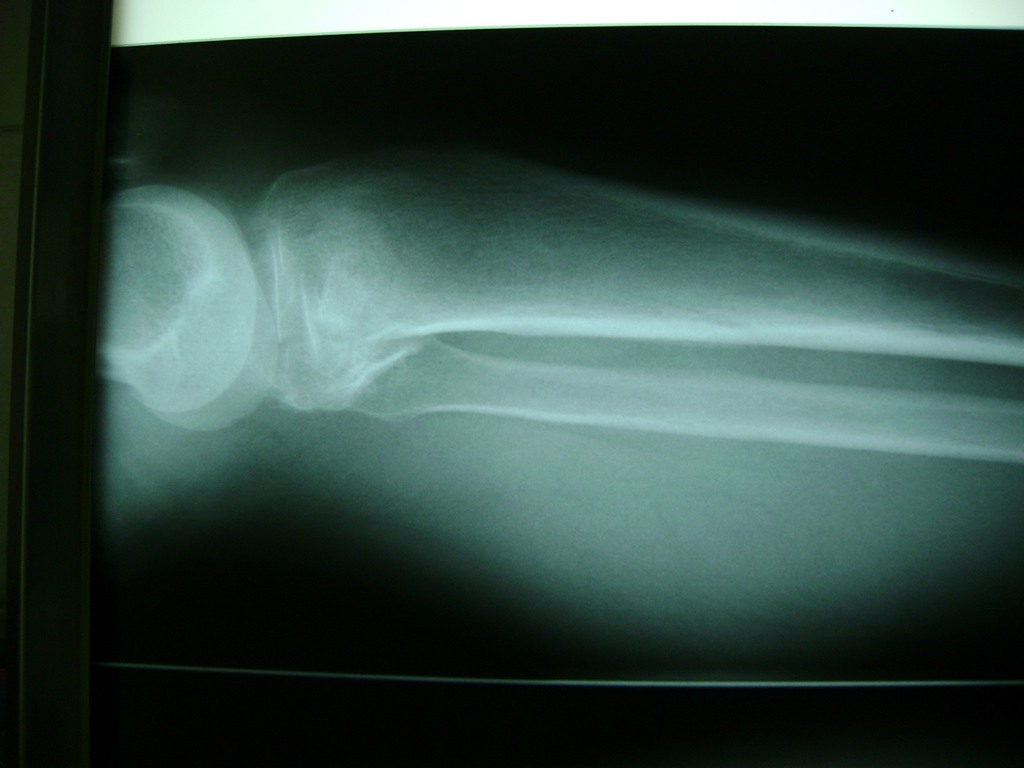

Tendón de Aquiles